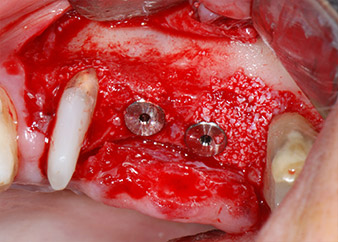

A continuación, los implantes (Restore, Keystone Dental, 3,75 mm de diámetro, 8,0 mm de longitud) se colocaron con el motor de implantes (figuras 11 y 12).

listos para los tornillos de cubierta

Fig. 12: Los dos implantes están colocados y listos para los tornillos de cubierta.

Las deficiencias óseas alrededor de los implantes, en el área mesial de la pieza 27 y alrededor de la raíz bucal de la pieza 24, se obturaron con partículas sustitutas de hueso xenógeno (Geistlich Bio-Oss) y se cubrieron con una membrana de colágeno absorbible (Geistlich Bio-Gide) a efectos de realizar un aumento mediante GBR

(figuras 13 y 14).